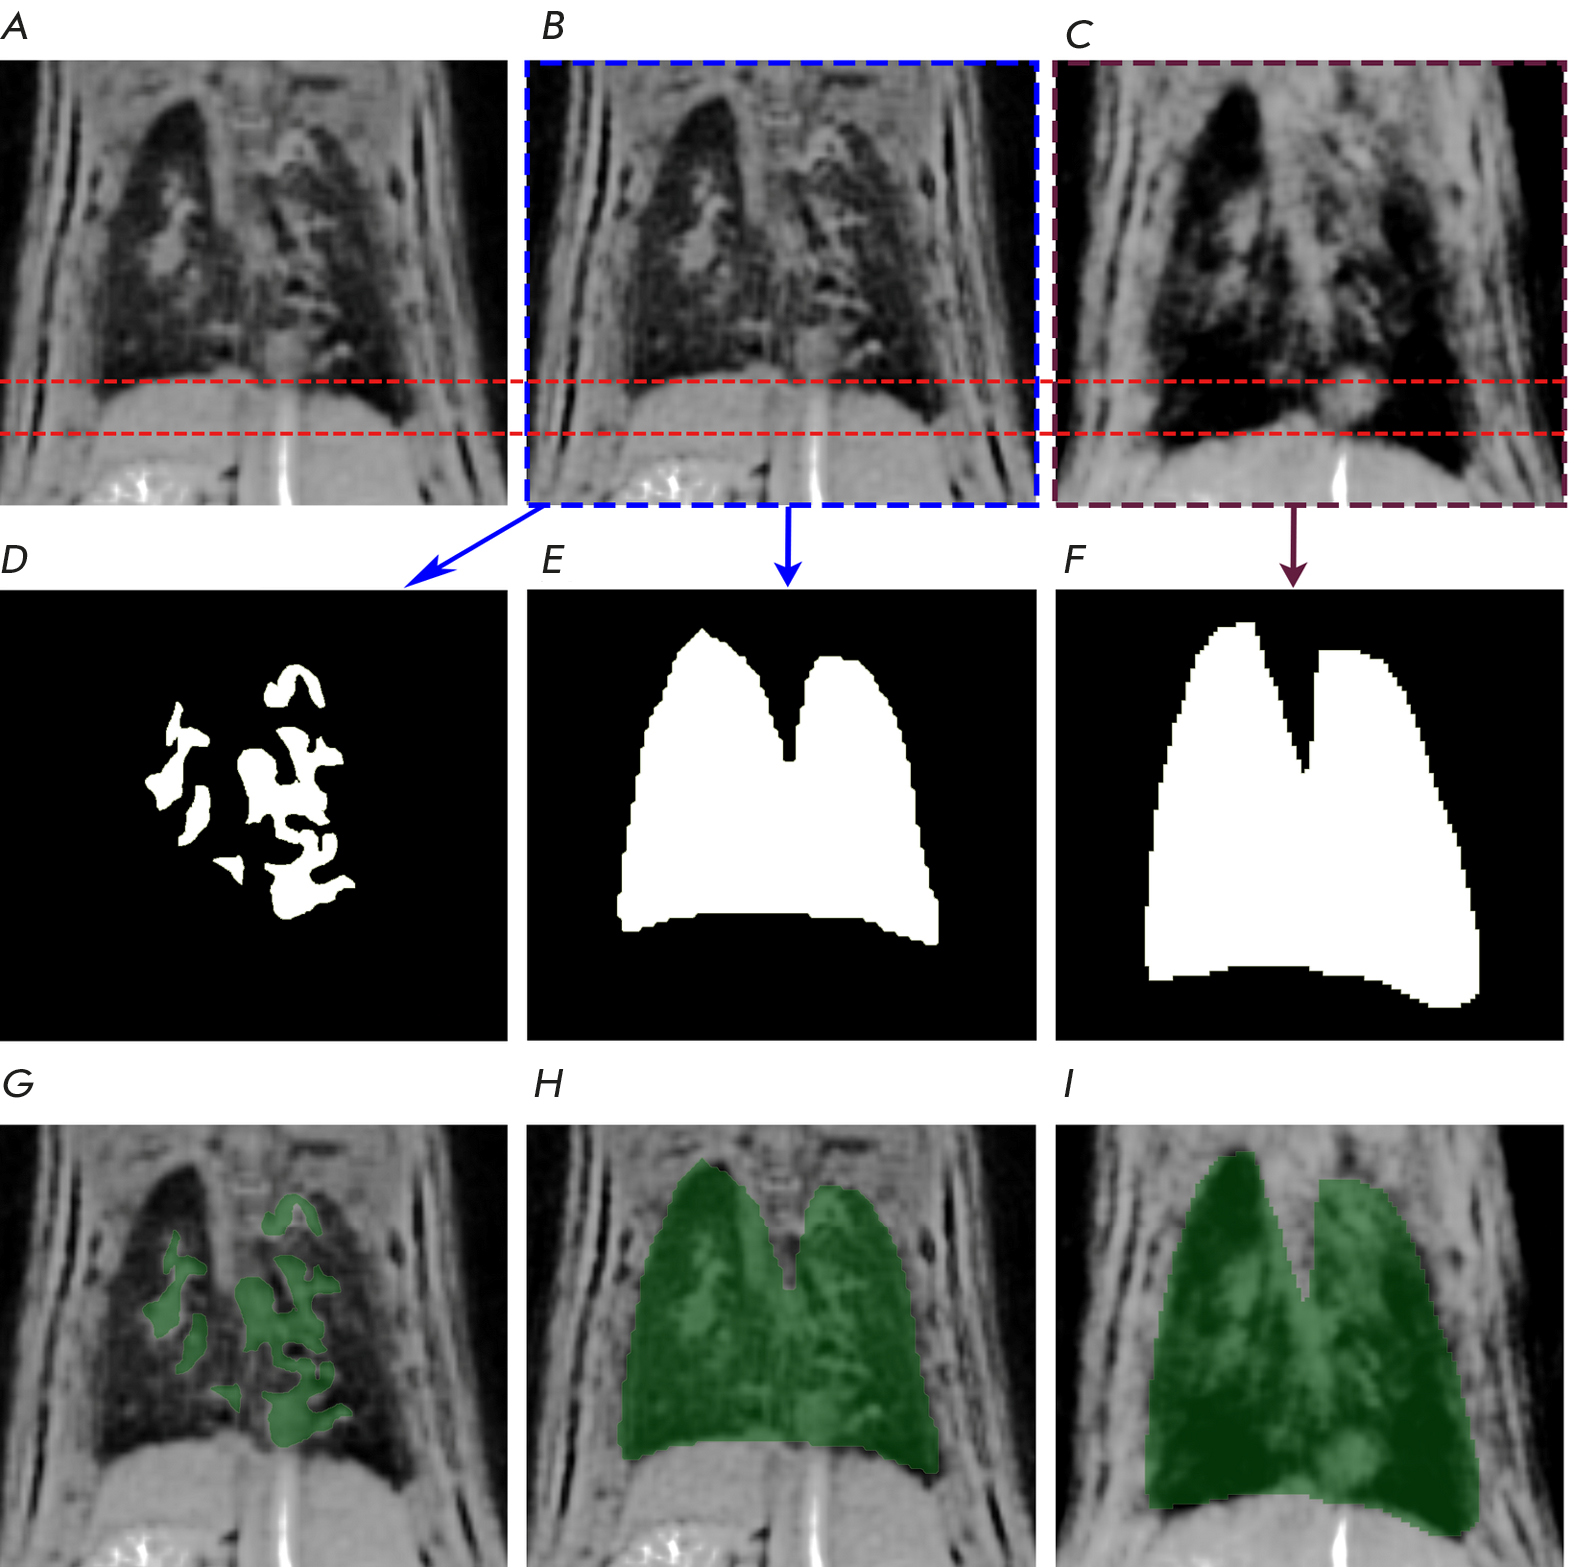

Примеры обработки результатов МРТ показаны на рис. 1.

Рис. 1. МРТ-снимки легких случайно выбранной крысы из группы с физиологическим раствором, а также соответствующие маски для легких и патологии. Данные представлены только для одного среза. A – исходное МРТ-изображение легких, Б – изображение фазы выдоха, В – изображение фазы вдоха, Г – маска патологии, Д – маска выдоха, Е – маска вдоха, Ж – маска патологии, наложенная на исходное МРТ-изображение легких, З – маска выдоха, наложенная на изображение выдоха, И – маска вдоха, наложенная на изображение фазы вдоха